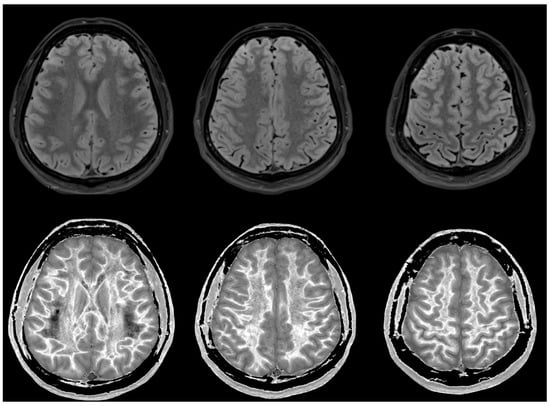

Figure 6 and Figure 7 show T2-FLAIR images (upper rows) with positionally matched dSIR images (lower rows). No abnormalities are seen in the white matter on the T2-FLAIR images, but very extensive high signal abnormalities are seen in the white matter of the corresponding dSIR images. There is relative sparing of the anterior central corpus callosum and, to a lesser extent, the posterior central corpus callosum. There is also some sparing of the peripheral white matter in the cerebral hemispheres.

Overall, the MRI findings in Case 2 are very similar to those in Case 1, as shown in Figure 4 and Figure 5. They have been described as a whiteout sign. This often involves 80% or more of the white matter in the cerebral and cerebellar hemispheres having an abnormal high signal appearance.

Figure 6. Case 2 was examined two years after his asphyxial episode. Comparison of positionally matched T2-FLAIR images (upper row) and narrow mD dSIR images (lower row). No abnormality is seen on the T2-FLAIR images, but there are extensive areas of high signals in the white matter of the brain. The anterior and posterior central corpus callosum and parts of the frontal lobes have a lower, more normal signal (darker appearance). Horizontal CSF flow artefacts are seen in the dSIR image in the middle lower row.